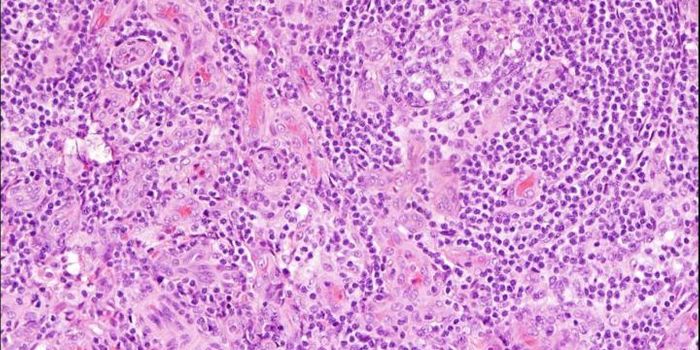

SEP 28, 2016ImmunologyA diet high in fat from specific sources is uniquely responsible for contributing to intestinal cancer through promoting ...